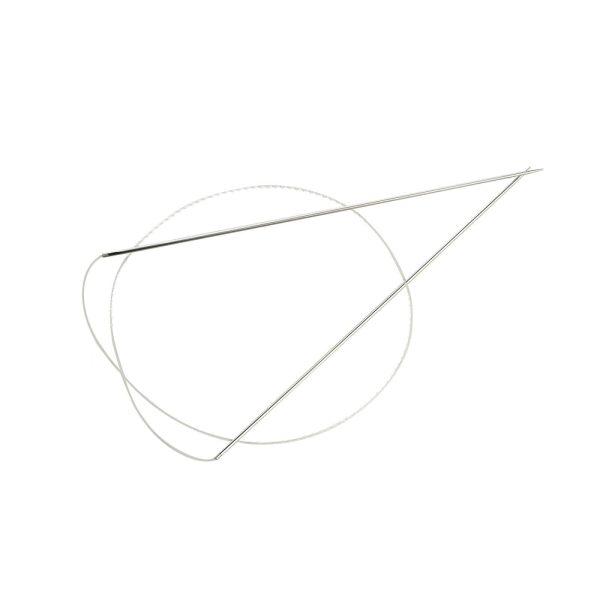

Velvet Dual Lift thread features a unique double needle for achieving a natural and immediate lifting effect in the desired area.

The thread is injected through a single injection site, which significantly reduces the damage to soft tissue.